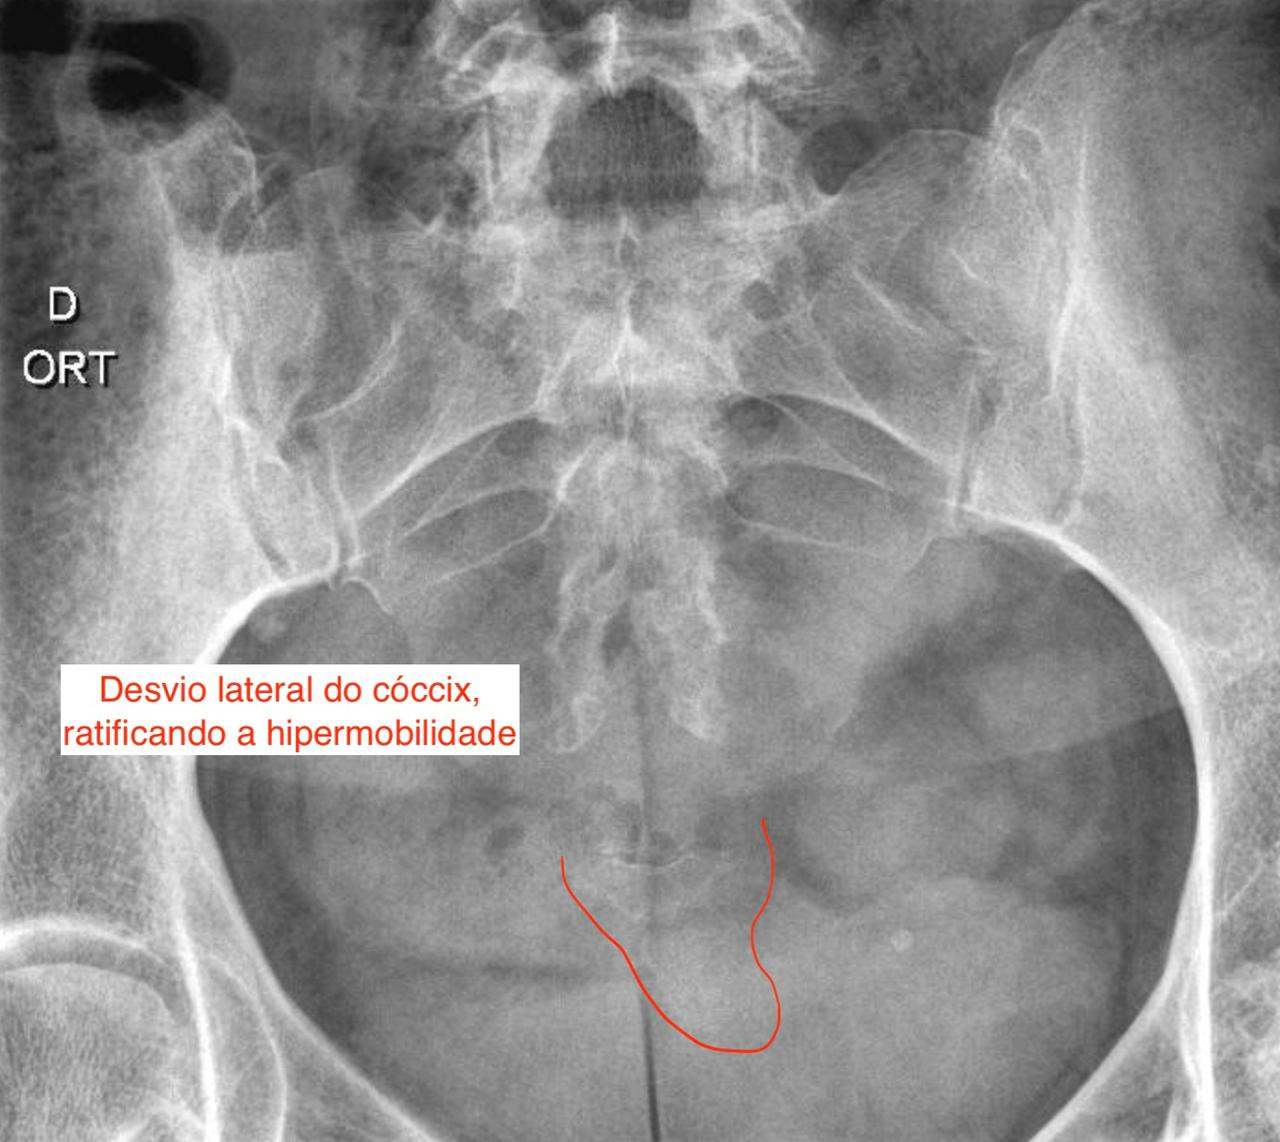

Resultado de Raio-x dinâmico em caso de suspeita de fratura do cóccix, evidenciando a hipermobilidade

Neste caso, o cóccix ainda apresentava desvio lateral

Durante a consulta, suspeitamos de fratura e solicitamos um raio-x dinâmico. O exame revelou um deslocamento do fragmento do cóccix, confirmando a fratura oculta.